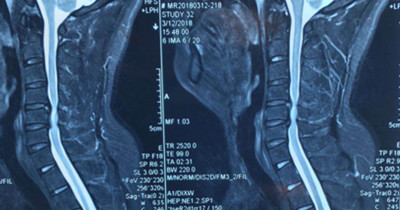

患者王先生,34岁,两个月来自觉行走时双下肢无力,伴踩棉花感,休息后症状无明显缓解,双手指麻木,呈加重趋势。一月前就诊于骨一科。确诊为颈椎病(脊髓型)。病变部位位于颈5-6平面。

图片一: